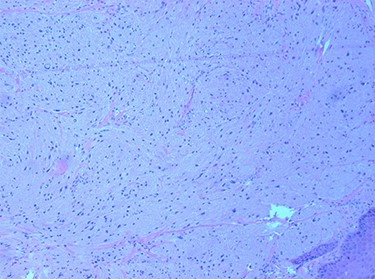

Histopathological examination revealed large cells with granular eosinophilic cytoplasm and nuclei with scattered mild to moderate atypia. These cells expressed CD68, CD56 and S100, and lacked expression of AE1 and AE3. Focal spindling of cells was present with no obvious necrosis or mitosis. The squamous surface epithelium was orthokeratizing with mild pseudoepitheliomatous hyperplasia (Figs 5 and 6).

tumour cells with abundant granular cytoplasm and sub-epithelial proliferation. H & E 100×.